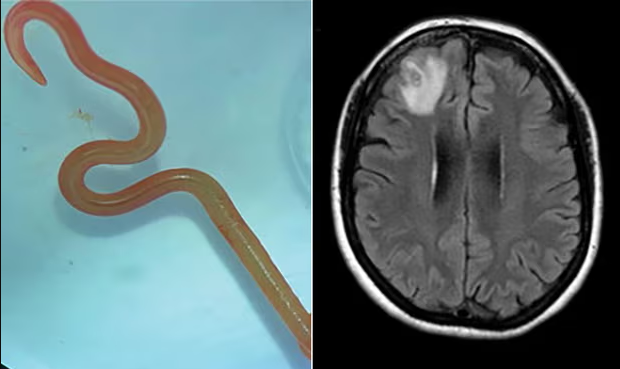

في حالة مثيرة للدهشة والأولى من نوعها في العالم، قام أطباء جراحة أعصاب في أوستراليا باستخراج دودة طفيلية طولها 8 سم من دماغ امرأة أوسترالية.

بعد تفاقم حالتها، أحالها الفريق الطبي إلى مستشفى كانبيرا جنوب أوستراليا، حيث كشف فحص التصوير بالرنين المغناطيسي لدماغها عن وجود تشوّهات تتطلّب عملية جراحية. والمفاجأة؟ اكتشاف وجود دودة حية داخل دماغ المريضة.

وفي هذا الصدد، وصف جرّاح الأعصاب الدكتور هاري باندي الأمر بأنه "من الأشياء التي لا تتكرر في الحياة المهنية للطبيب مرتين". كما أرسلت الدودة الحية إلى مختبر متخصص يتمتع بخبرة كبيرة في مجال الطفيليات.

كشف المختبر عن أن نوع الدودة الطفيلية المستديرة، هو أوفيداسكاريس روبرتسي، وهي دودة طفيلية توجد عادة في الثعابين. وما حدث لهذه السيدة يعتبر الحالة الأولى من نوعها بين البشر.